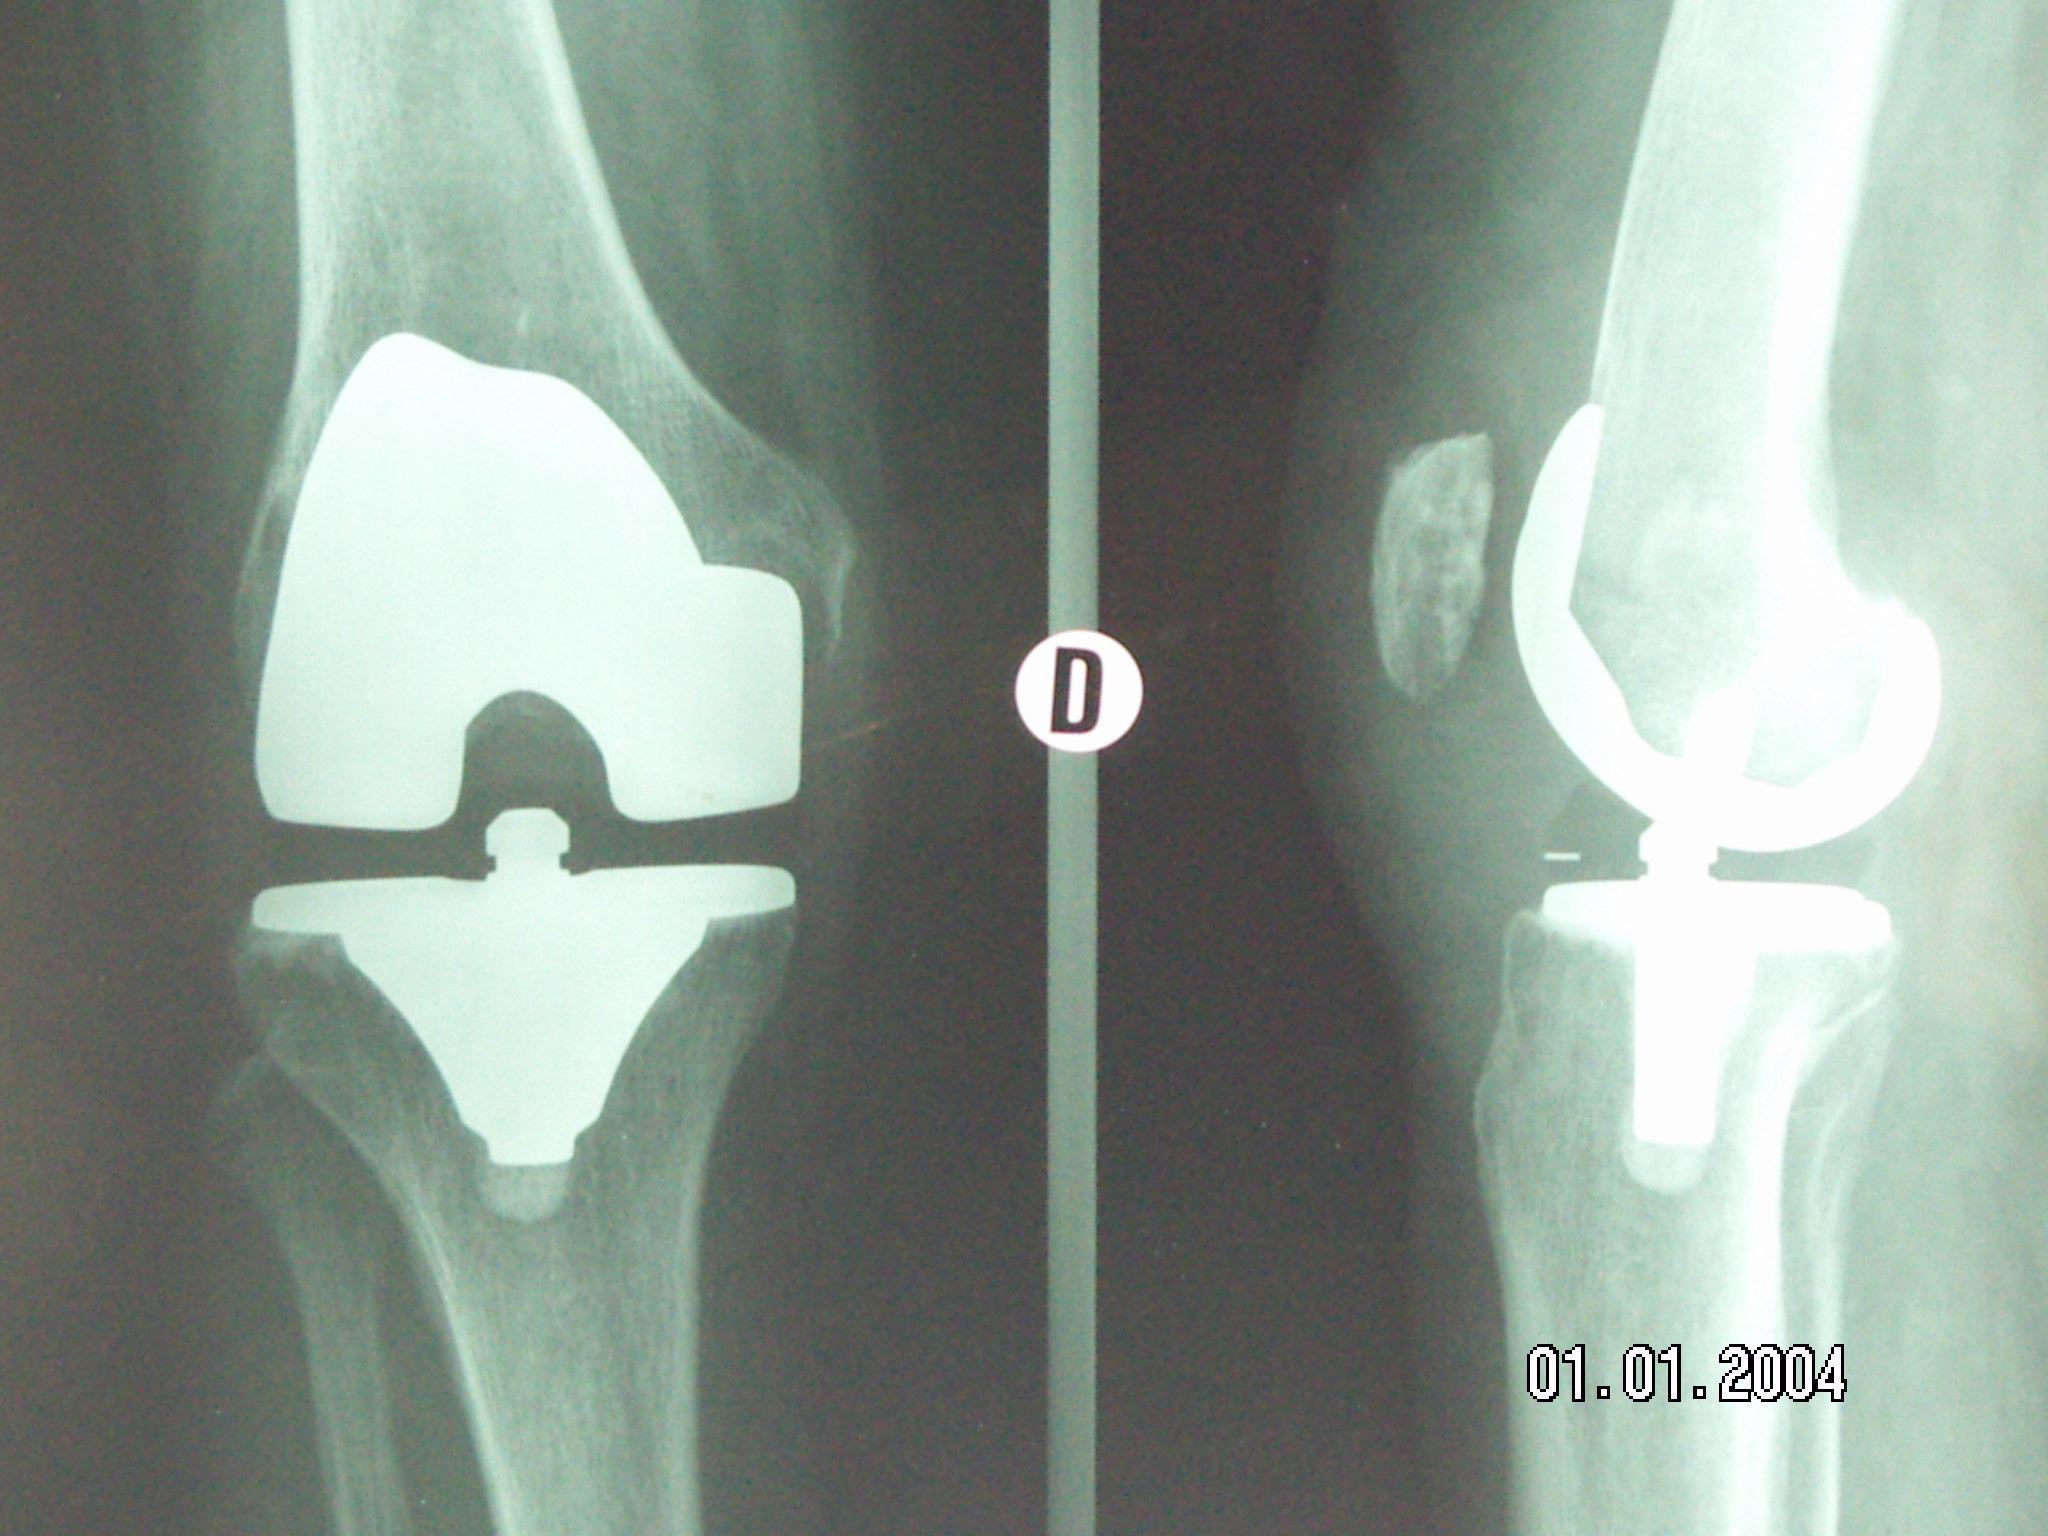

Prothèse GENOU Chirurgie orthopédique Dr. Burn from orthopedie-burn.ch

Prothèse GENOU Chirurgie orthopédique Dr. Burn Lorsque la douleur et la gêne deviennent insupportables, la prothèse de genou peut être envisagée comme solution J'ai une arthrose importante du genou droit à seulement 43 ans Introduction Les problèmes de genou sont fréquents chez de nombreuses personnes, qu'elles soient jeunes ou âgées